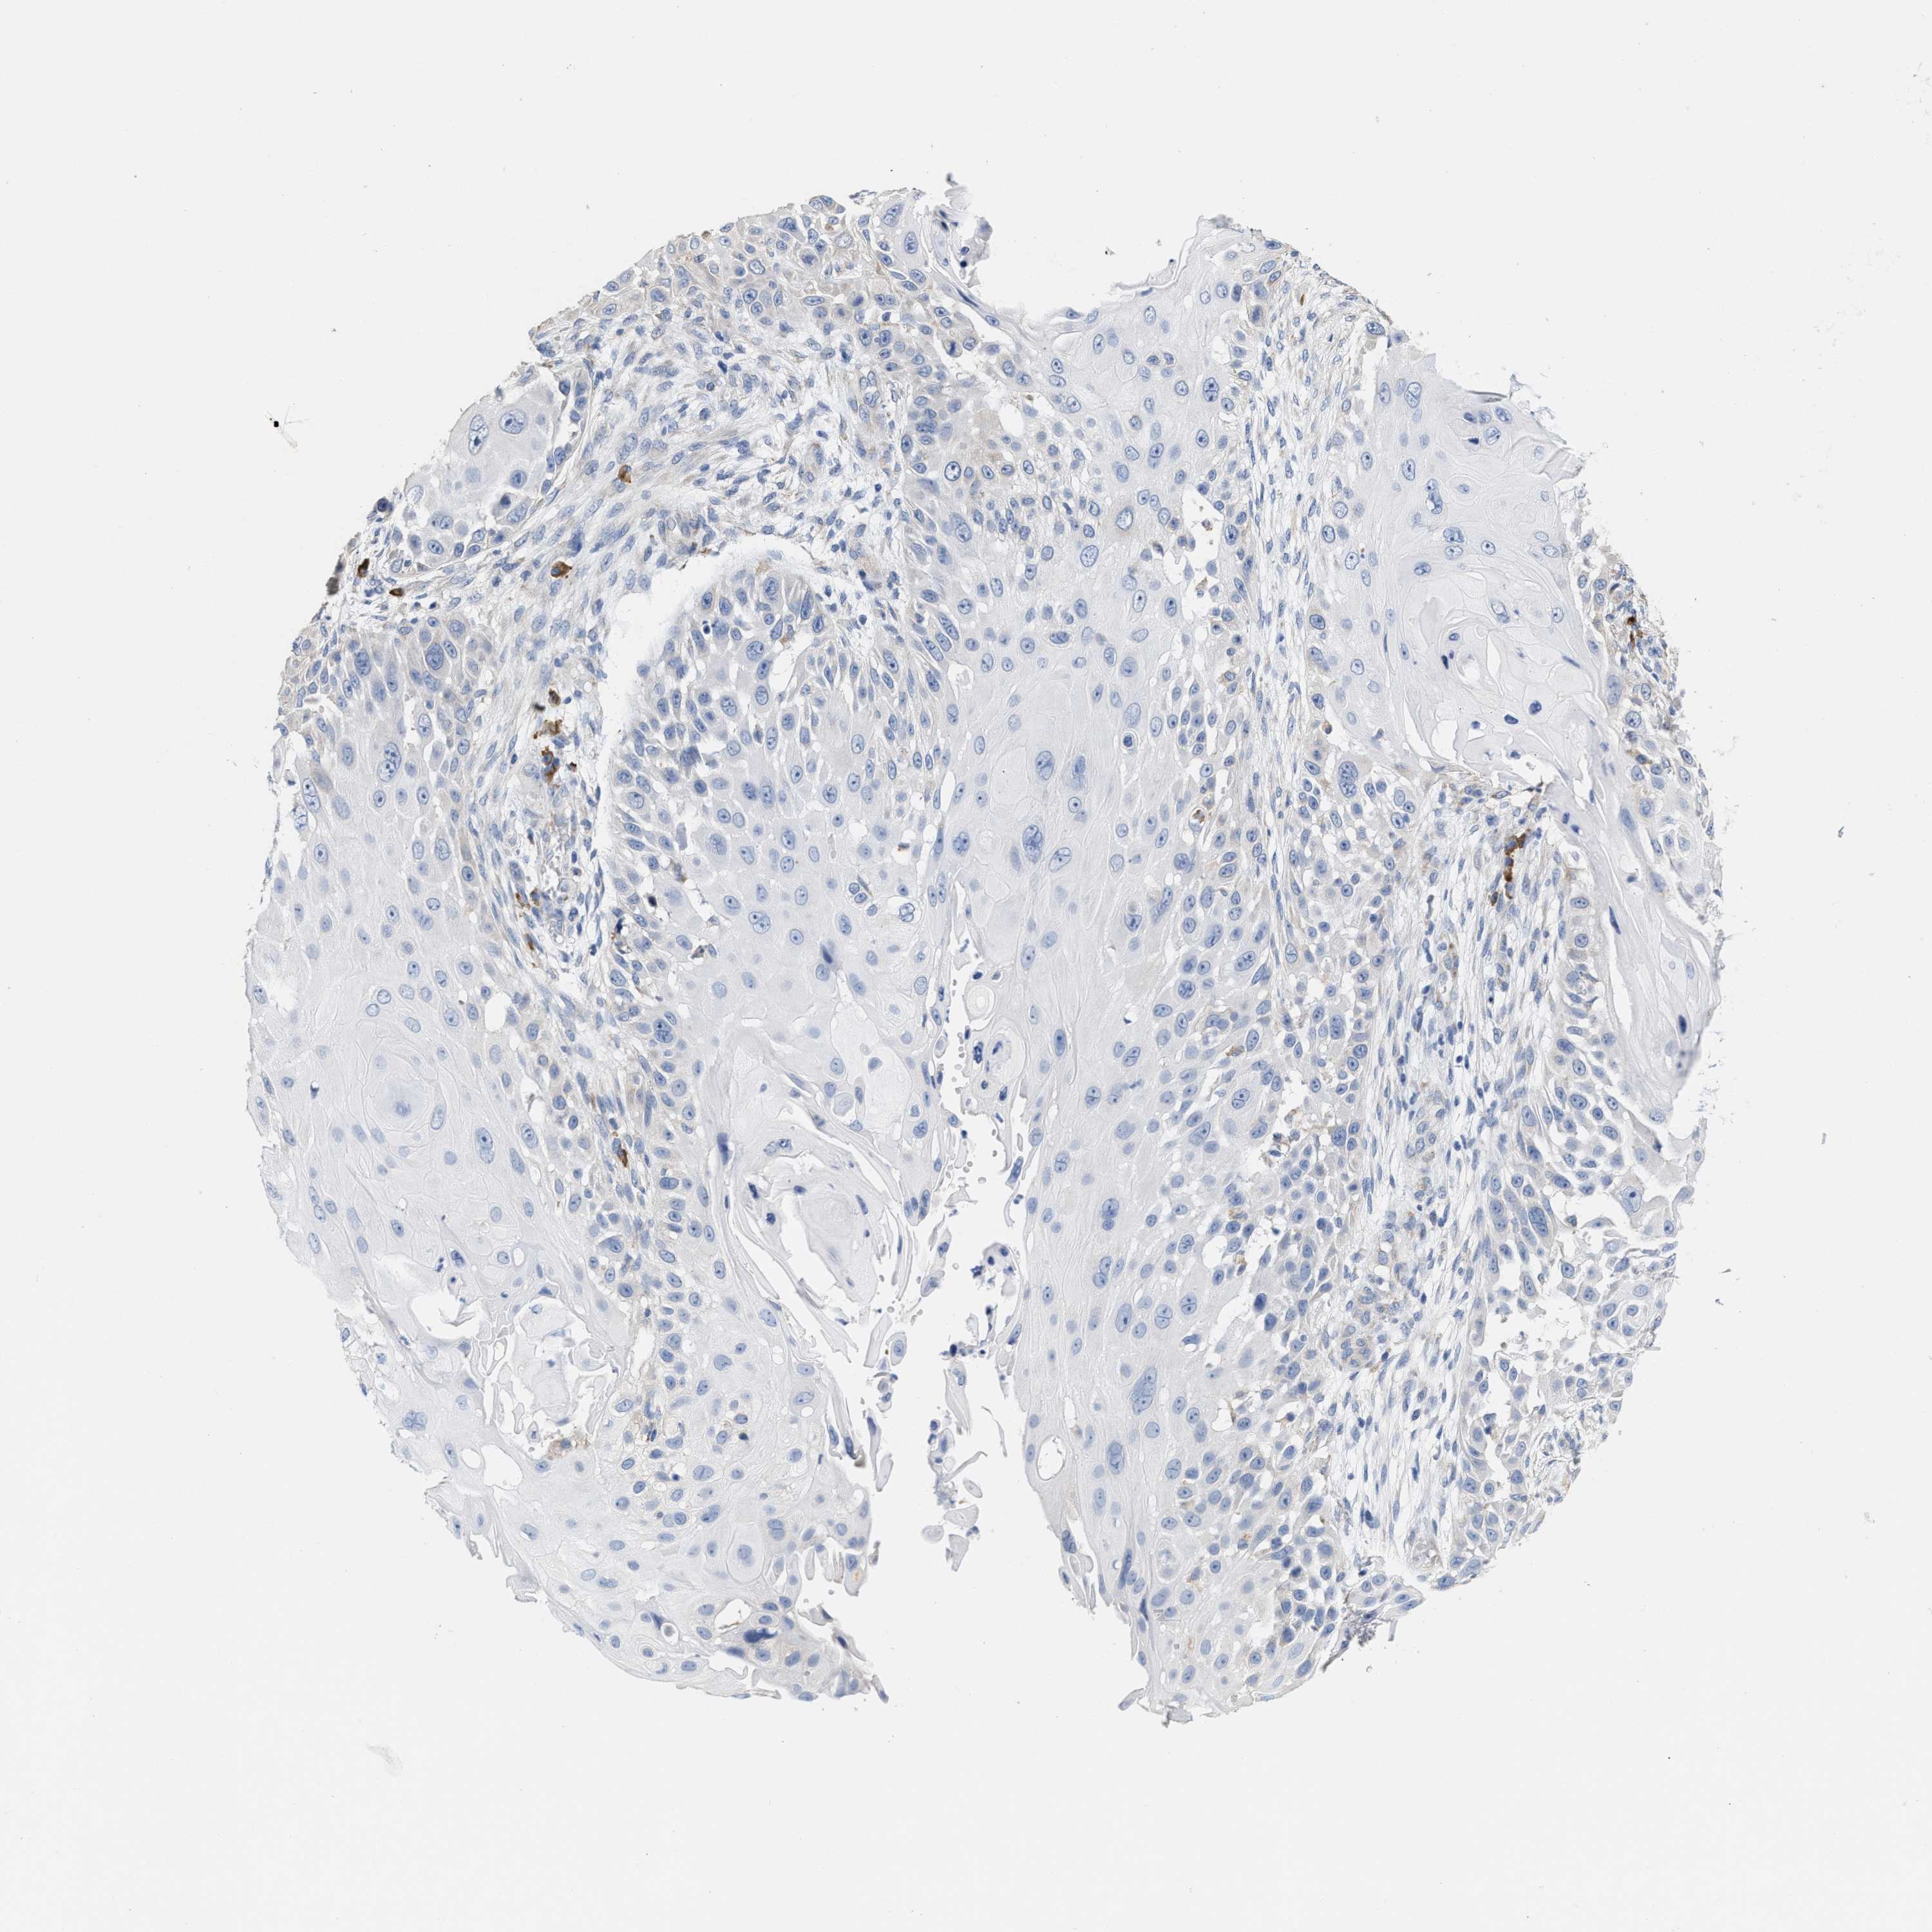

Basal cell and squamous cell cancer

SKIN CANCER - Protein expressioni

A mouse-over function shows sample information and annotation data. Click on an image to view it in a full screen mode. Samples can be filtered based on level of antibody staining by selecting one or several of the following categories: high, medium, low and not detected. The assay and annotation is described here.

Antibody stainingi

Antibody staining in the annotated cell types in the current human tissue is reported as not detected, low, medium, or high, based on conventional immunohistochemistry profiling in selected tissues. This score is based on the combination of the staining intensity and fraction of stained cells.

Each image is clickable and will lead to virtual microscopy that enables deeper exploration of all samples and also displays staining intensity scores, fraction scores and subcellular localization as well as patient and tissue information for each sample.

Antibody HPA020028

Staining

High

Medium

Low

Not detected

Intensity

Strong

Moderate

Weak

Negative

Quantity

>75%

75%-25%

<25%

None

Location

Nuclear

Cytoplasmic/membranous

Cytoplasmic/membranous,nuclear

Basal cell carcinoma

Squamous cell carcinoma, NOS

Squamous cell carcinoma, metastatic, NOS